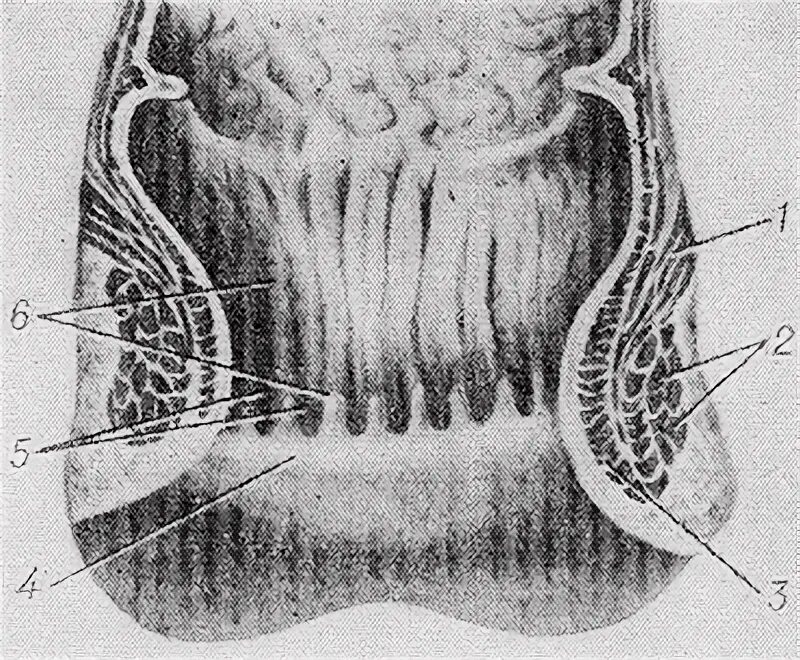

Мышца поднимающая задний проход